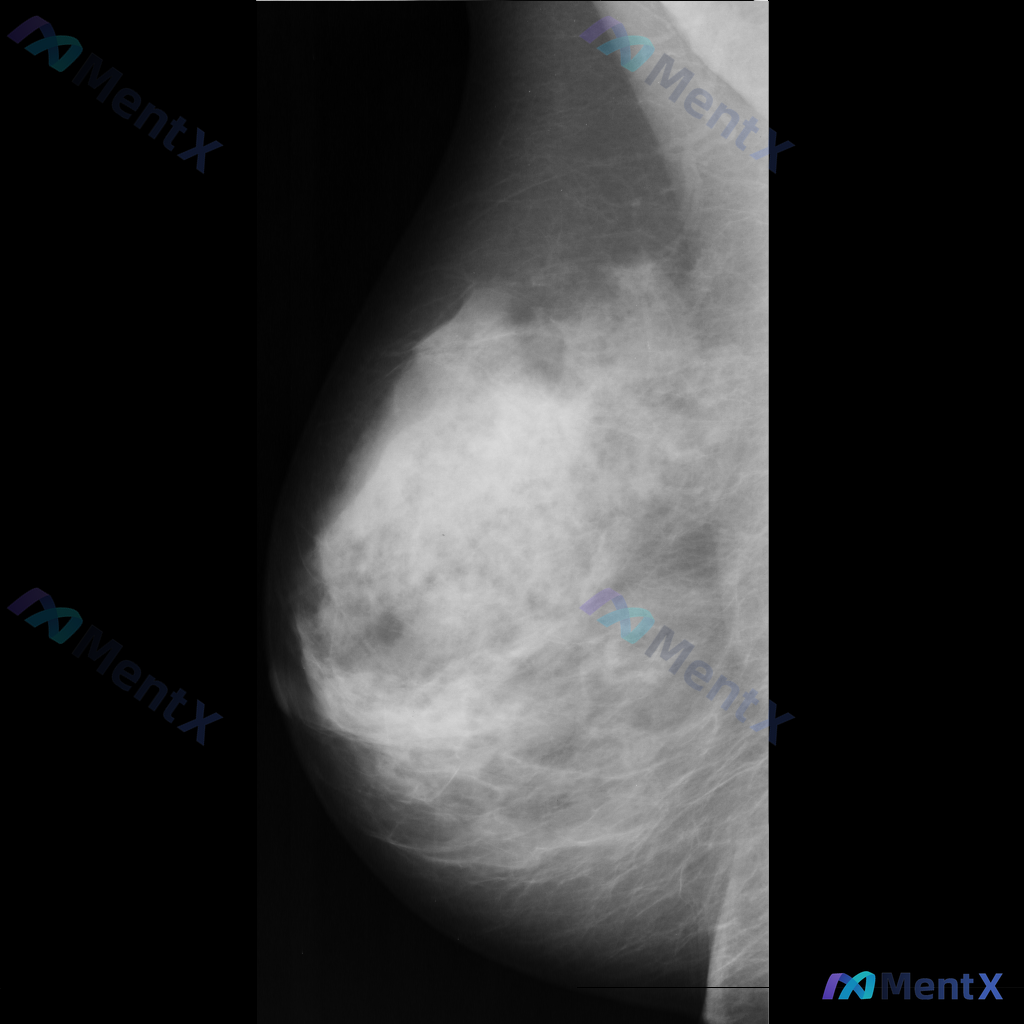

整理到一张乳腺钼靶影像资料,大家一起讨论下。 影像表现大概是这样: - 异常区域位于乳腺下象限偏外侧 - 可见一局限性致密影,形态大致呈卵圆形或不规则形 - 边缘部分清晰,局部可能模糊或有细微毛刺样改变 - 致密影密度高于周围脂肪组织,与纤维腺体组织密度相似或略高 - 周围乳腺小梁结构似有轻微的牵拉...